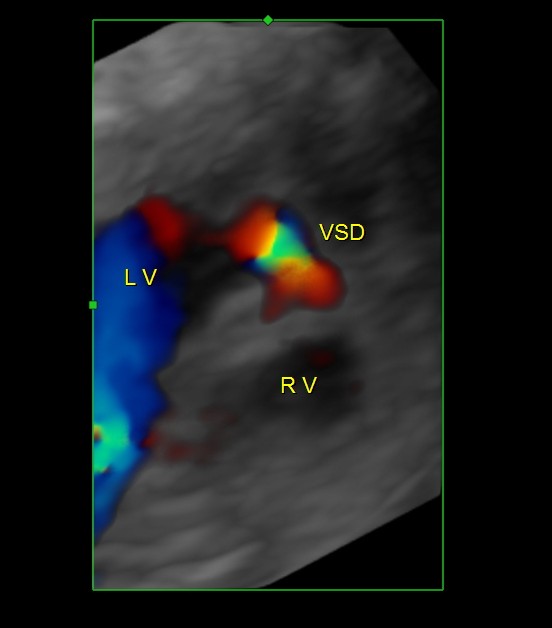

This is a review scan done for a 21 year old primi and now the gestational age is around 34 to 35 weeks . Earlier scan revealed a muscular VSD and some of the images were published in this blog a few weeks ago.

The following two images are glass body colour flow reconstruction

At present the fetus has asymmetrical IUGR ; All other parameters are normal